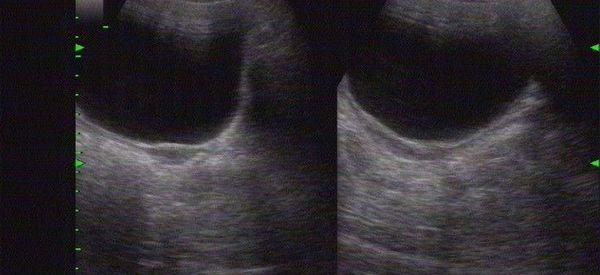

做试管婴儿的前提是要子宫发育正常,否则胚胎在子宫里没有发育的基础,即使着床了也没有办法成长,如果只是子宫偏小,还有怀孕的可能,但始基子宫是绝对不会怀孕的,再加上没有来过月经,也不适合受精卵移植。

3、女方子宫条件满足,内膜环境很重要;

始基子宫目前没有特效的治疗方法,对于有子宫腔和内膜、没有阴道的始基子宫,可以行阴道成形术,然后用雌激素来促进子宫发育。

始基子宫想要孩子,也只能通过第三方辅助生殖的方式来实现,因为始基子宫患者一般没有宫腔、没有内膜、也没有月经,即使治疗之后,也不具备胚胎生长发育的场所。